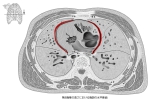

The mediastinal surface of the lung presents a deep concavity, the cardiac impression, which accommodates the pericardium; this is larger and deeper on the left than on the right lung, on account of the heart projecting farther to the left than to the right side of the median plane.